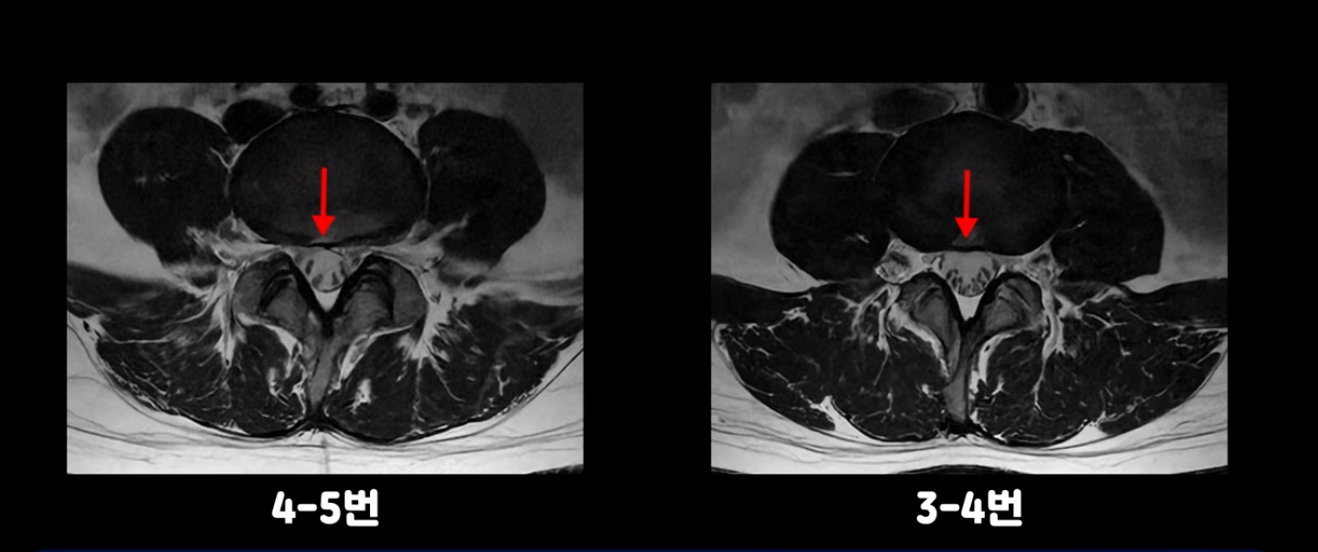

우선 이분 허리 MRI를 보면 5번 1번에 퇴행성 디스크가 있지만 방사통을 일으킬 만큼 신경을 누르고 있어 보이지 않습니다.

오른쪽으로 디스크가 약간 찢어져 보이는데, 작년에 찍은 MRI에서도 보이는 것이라 오래 전에 찢어진 후 아문 흔적으로 보입니다.

중요한 것은 오른쪽 다리에 심한 방사통이 있다든가 재채기를 못 한다거나 허리를 구부리거나 몸을 살짝 비틀 때 날카로운 통증이 없습니다. 즉, 섬유륜이 최근에 찢어진 게 아닌 겁니다.

4번 5번과 3번 4번 마디도 디스크가 중앙으로 살짝 밀려나와있지만 최근에 섬유륜이 찢어진 것도 아니고, 신경 다발을 누를 정도로 심하게 밀려나와 있는 것도 전혀 아닙니다.

양쪽 신경 가지가 빠져나가는 추간공도 충분히 넓어서 신경학적 방사통을 일으킬 여지가 없습니다.